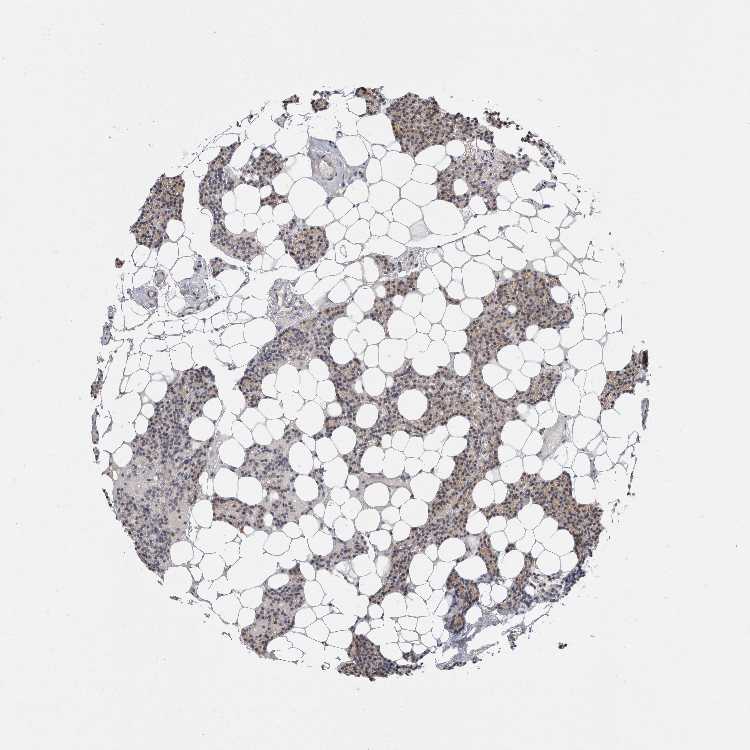

PARATHYROID GLAND - Antibody stainingi

Antibody staining in the annotated cell types in the current human tissue is reported as not detected, low, medium, or high, based on conventional immunohistochemistry profiling in selected tissues. This score is based on the combination of the staining intensity and fraction of stained cells.

Each image is clickable and will lead to virtual microscopy that enables deeper exploration of all samples and also displays staining intensity scores, fraction scores and subcellular localization as well as patient and tissue information for each sample.

Antibody HPA026687

Glandular cells Low

PARATHYROID GLAND - HPA RNA-seqi

The RNA-seq details section shows detailed information about the individual samples used for the transcript profiling and results of the RNA-seq analysis.

Information about each individual sample is listed below, including gender, age, a tissue section image and estimated fractions of cell types. nTPM (normalized transcripts per million) values give a quantification of the gene abundance which is comparable between different genes and samples.